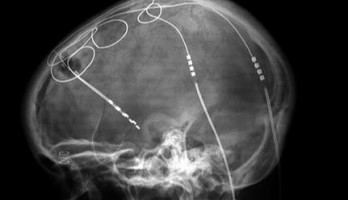

| Belgische wetenschappers zijn er in geslaagd een zogenaamde hersen-pacemaker te hacken. Ze tonen aan dat de controle over de neurostimulator...